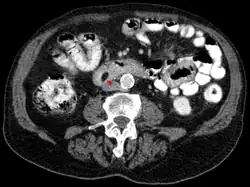

Die radiologische Beurteilung ist in bis zu 71 Prozent der Fälle diagnostisch. Die Computertomographie (CT) und speziell die Magnetresonanztomographie (MRT) sind als bildgebende Verfahren in der Einschätzung des Tumors hilfreich. Im MRT sind Lipome – unabhängig von der gewählten Pulssequenz – isointens (gleiche Signalintensität) mit dem subkutanen Fettgewebe. Mit Ausnahme der um das Lipom befindlichen Kapsel erhöht sich der Kontrast bei der Gabe eines Kontrastmittels – beispielsweise Gadotersäure – nicht. In 37 bis 49 Prozent der Fälle ist im CT oder MRT ein dünnes Septum von weniger als 2 mm zu erkennen, was als nahezu pathognomonisch für die Diagnose eines Lipoms gesehen wird.[6][20] Die wesentlichen Kriterien zur Unterscheidung zwischen gutartigem Lipom und bösartigem Liposarkom sind in den meisten Fällen das Fehlen eines Septums, das Vorhandensein von mineralisierten Bereichen und die Interdigitation (eine Verzahnung benachbarter Zellen durch fingerförmige Zellfortsätze) mit der Skelettmuskulatur (Ausnahme: intramuskuläre Lipome).[6][7] Selbst erfahrene Diagnostiker können ein Lipom aber nur in 79 % der Fälle richtig von einem Liposarkom unterscheiden. Es wird daher vorgeschlagen, diese Tumoren in der Bildgebung grundsätzlich als niedriggradige Fetttumoren zu bezeichnen.[21]